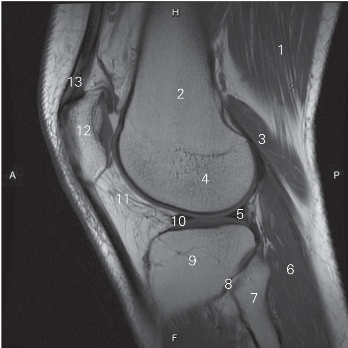

图5-27 经股骨外髁的矢状断层MR T1加权图像

1 股二头肌 biceps femoris 2 股骨 femur

3 腓肠肌外侧头 lateral head of gastrocnemius

4 股骨外侧髁 lateral condyle of femur

5 外侧半月板后角 posterior horn of lateral meniscus

6 跖肌 plantaris 7 腓骨头 head of fibula

8 胫腓上关节 superior tibiofibular joint 9 胫骨 tibia

10 外侧半月板前角 anterior horn of lateral meniscus

11 髌下脂肪垫 infrapatellar fat pad 12 髌骨 patella

13 股四头肌肌腱 quadriceps tendon